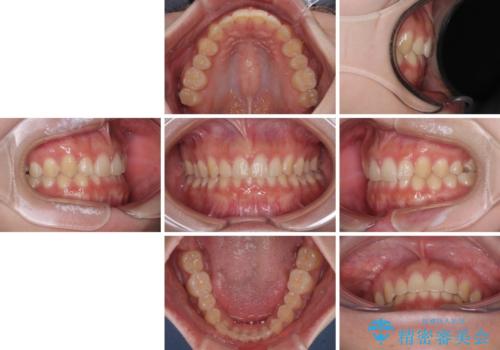

前歯のすきっ歯を治したい インビザラインによる矯正治療

- 上顎前歯の隙間を気にして来院された患者様です。

目立たない装置を希望とのことで、インビザラインを用いて矯正治療を行うこととしました。

最終的には隙間は全て閉じ、綺麗な仕上がりとなりました。